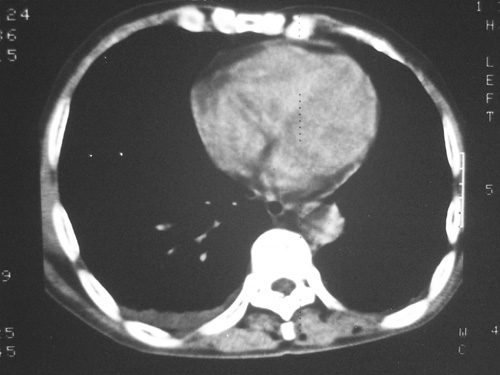

老年男性,70岁。煤矿工人20年。一周前咳嗽、发烧,拍x片考虑矽肺可能。始终咳嗽行ct检查,发现弥漫性病变,似感染但密度很高,细支气管肺泡癌无法排除,请老师给予指点。

一般矽肺多为双肺融合状,团块状高密度结节影.并散在多处小结节影.可这个病人只表现在单肺,并没有融合结节影.一周前的x片没显示大片高密度影,可定位扫描时(图象忽略传了),右肺已经清晰显示大片高密度影.作比较感觉是新病灶.可实际表现又不象,所以才拿来让各位老师看看.

矽肺合并右肺结核可能性大.右侧少量胸腔积液.